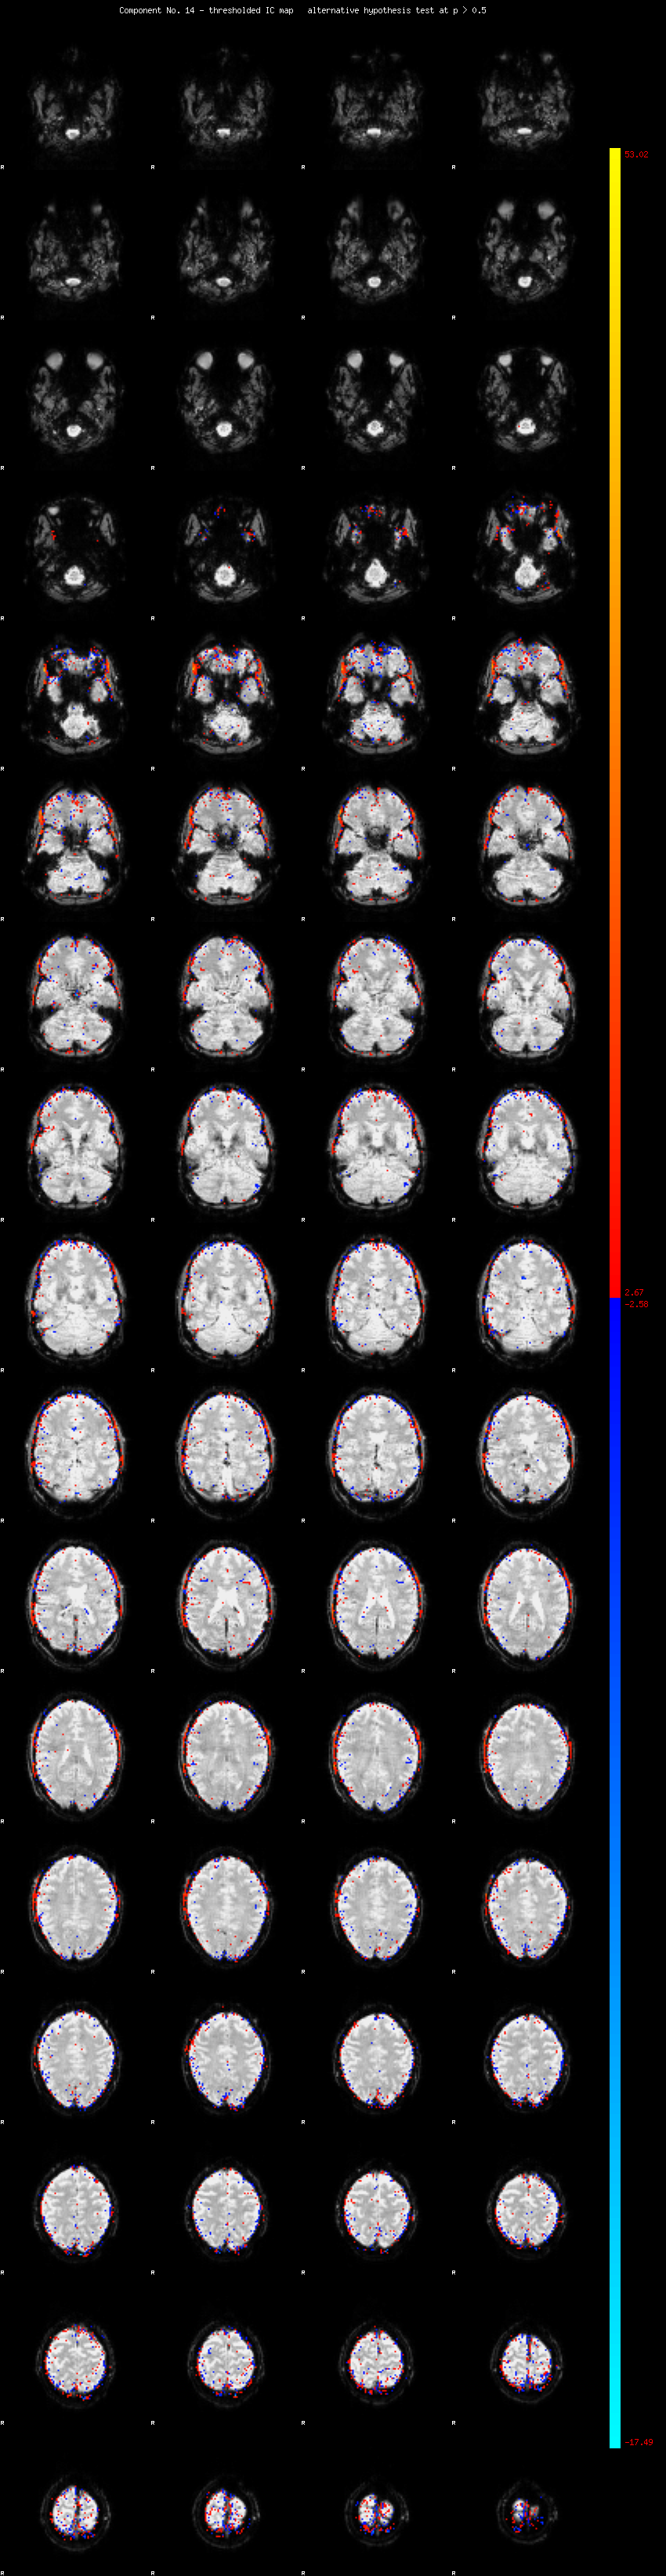

MELODIC Component 14

1.75 % of explained variance;     1.16 % of total variance

MMfit